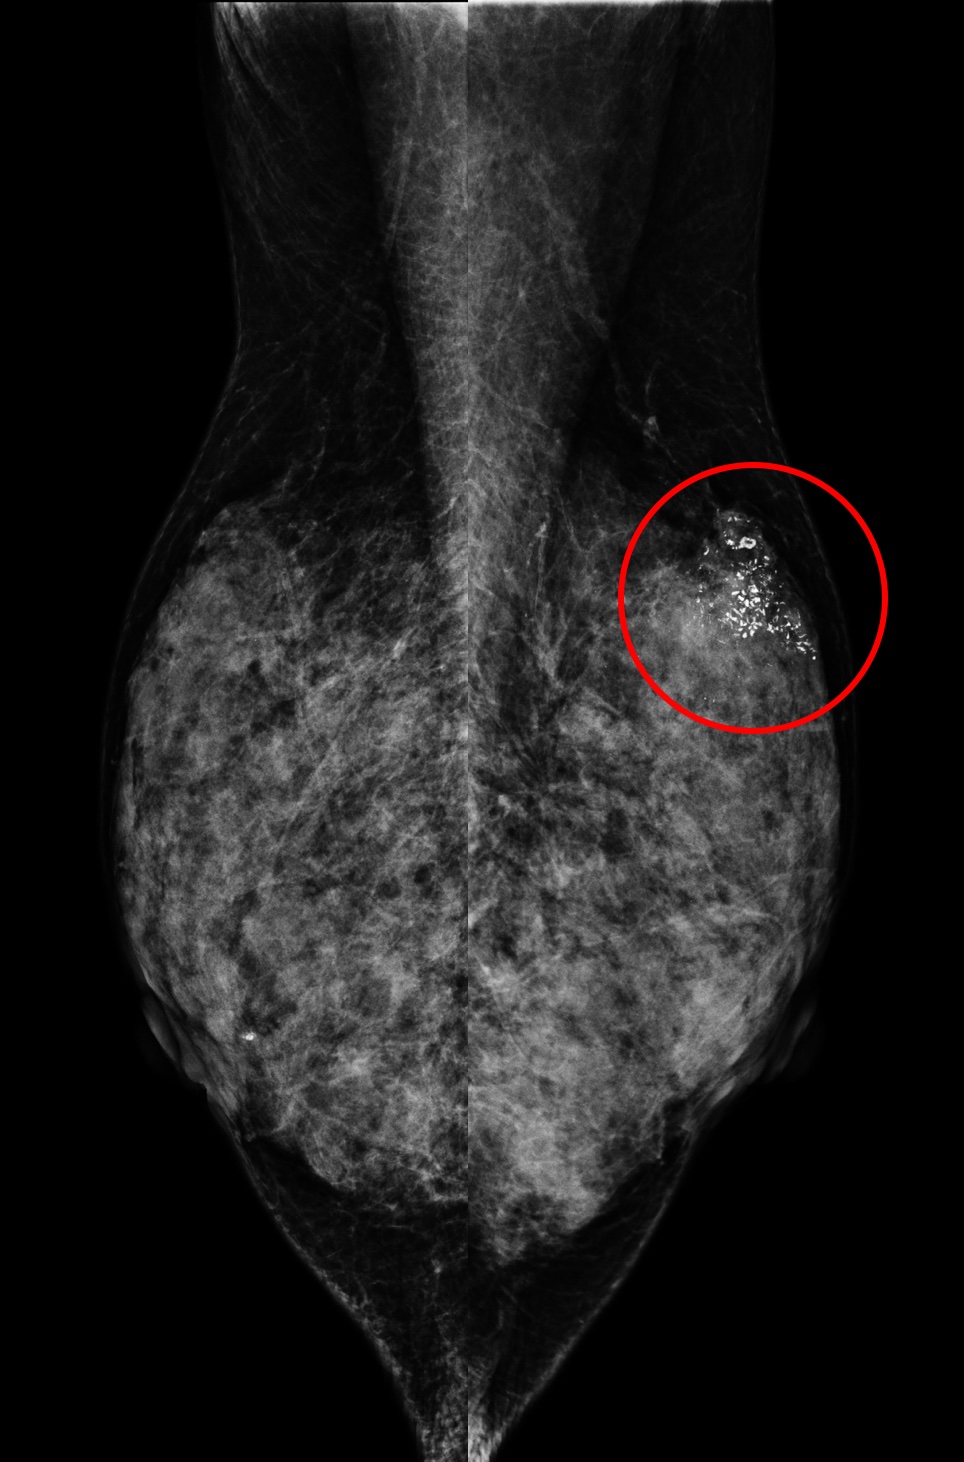

(A) 61歲女性於國健署「乳房攝影篩檢」發現:左乳上方有一不尋常的群聚鈣化點、經手術證實為乳房原位癌,後續恢復良好。

另一名55歲女性於國健署「乳房攝影篩檢」發現:左乳下方有一局部腫塊合併組織變形,經切片證實為早期乳房侵襲癌。